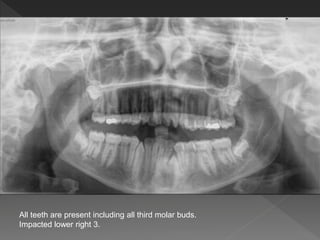

All teeth are present including all third molar buds.

Impacted lower right 3.

Clinically :

Palpation  no labial or lingual bulge

X ray : parallex techinique

SLOB  within the line of the arch